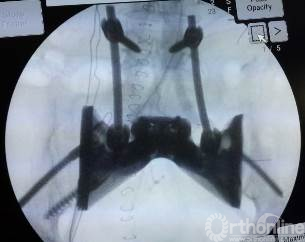

目前方兴未艾的3D打印技术为破解难题打开的新的大门。为了最大程度重建王力的骶骨缺损、恢复腰骶部连续性,保证术后的生活质量,郭卫教授应用3D打印技术,根据该患者骶骨切除术后骨缺损定制制造出空间结构解剖形态的人工全骶骨假体,其表面具有金属孔隙结构,可以允许骨细胞长入空隙金属内,假体与脊柱、骨盆连接,更符合生物力学结构的功能重建。

整台手术历时4小时成功完成,骶骨肿瘤彻底切除后,经过精心设计、反复修改的“高订”假体完美安放,与腰椎、骨盆紧密贴合,固定精准牢靠。国际首例应用3D打印特殊定制人工全骶骨假体进行骨缺损重建实现了完美首秀。这一假体及重建方式均为世界首创,为骶骨恶性肿瘤切除后骨缺损的重建方式开辟了一条崭新的途径。